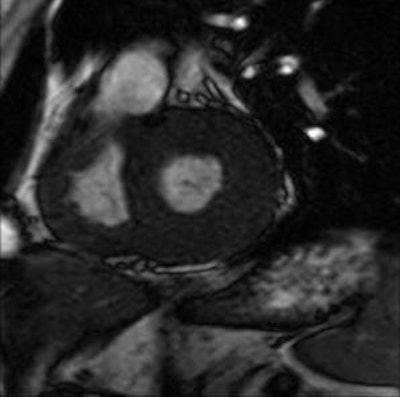

![]() |

| Cardiac involvement in 38-year-old man. Late-enhancement T1-weighted cardiac image in short axis (1.5-tesla system, 3D inversion recovery T1-weighted multishot gradient echo; TR/TE, 3.9/1.4; flip angle, 25°; inversion-recovery prepulse delay, 200 msec) shows band of hyperenhancement assumed to be related to myocardial fibrosis in upper part of septum (large arrows) and subepicardial nodules in inferior wall (small arrows). Cine MRI image at same level (not shown) displayed normal segmental contraction. |

The imaging protocol "must include cine MRI steady-state free-precision sequences in short-axis, long-axis, and four-chamber views; and delayed-enhanced T1-weighted sequences in at least the short-axis view," the authors stated (AJR, April 2006, Vol. 186:4, pp. 1184-1191).

Almost all Fabry's disease patients -- men in particular -- display left ventricular (LV) hypertrophy, brought on by focal myocardial fibrosis, which gives off an abnormal signal. Lidove's group stressed the importance of measuring LV mass at initial presentation as this information must be monitored as a prognostic indicator of therapy, the group said.